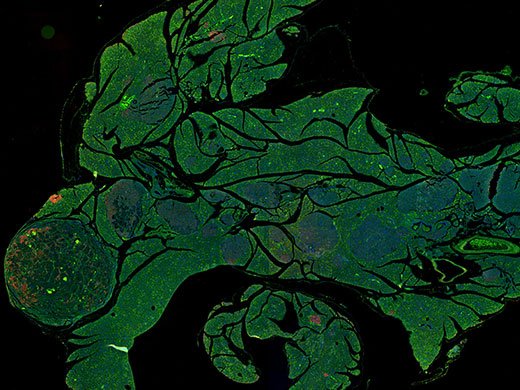

药物研发使用Dapi、GFP和RFP染色的胰腺。 图像数据承蒙新泽西州罗格斯癌症中心的Wenjin Chen提供。 |